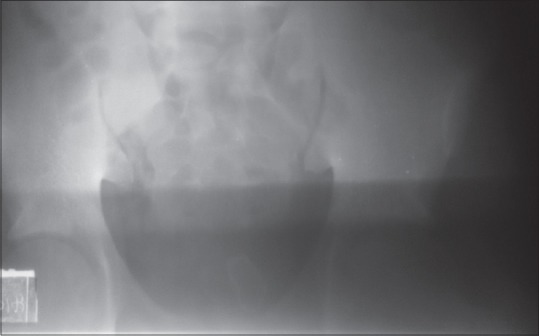

膀胱内异物的报道是罕见的。已经检索到各种对象。诊断主要根据下尿路症状和下腹痛病史,并结合相关影像学检查。治疗取决于物体的大小、性质和结构。该方法可能是内窥镜或通过开放手术取决于上述突出的因素。

Reports of foreign body in the bladder are rare. Various objects have been retrieved. Diagnosis is mainly by history of lower urinary tract symptoms and low abdominal pain combined with relevant radiological investigations. Treatment depends on the size, nature, and configuration of the object. The approach may be endoscopic or through open surgery depending on the above highlighted factors.